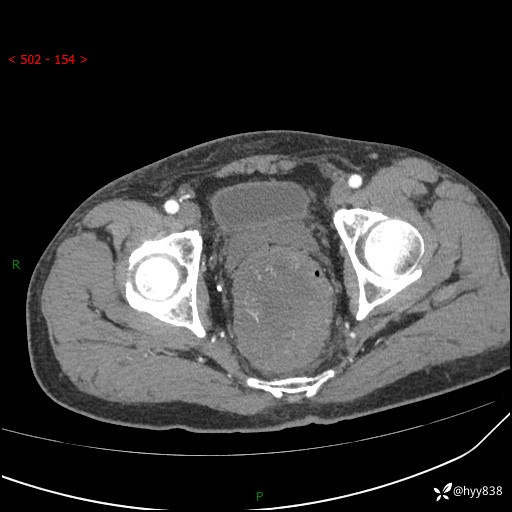

盆腔CT平扫+增强